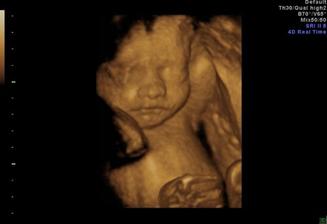

15.3.2009 - 4D ultrazvuk NADHERA :o) naše modelka se nám ukázala v plné kráse....měli jsme štěstí, že byl krásně vidět obličej a nožičky a ručičky se všema prstíkama ;o) no prostě se předvedla na jedničku :o) ale asi po půl hodině usoudila, že už to stačilo a normálně na nás vystrčila prďku a zabořila obličej do placenty :o) tak jsme jí teda nechali už na pokoji a šťastní jsme odcházeli s fotečkama a s DVD....